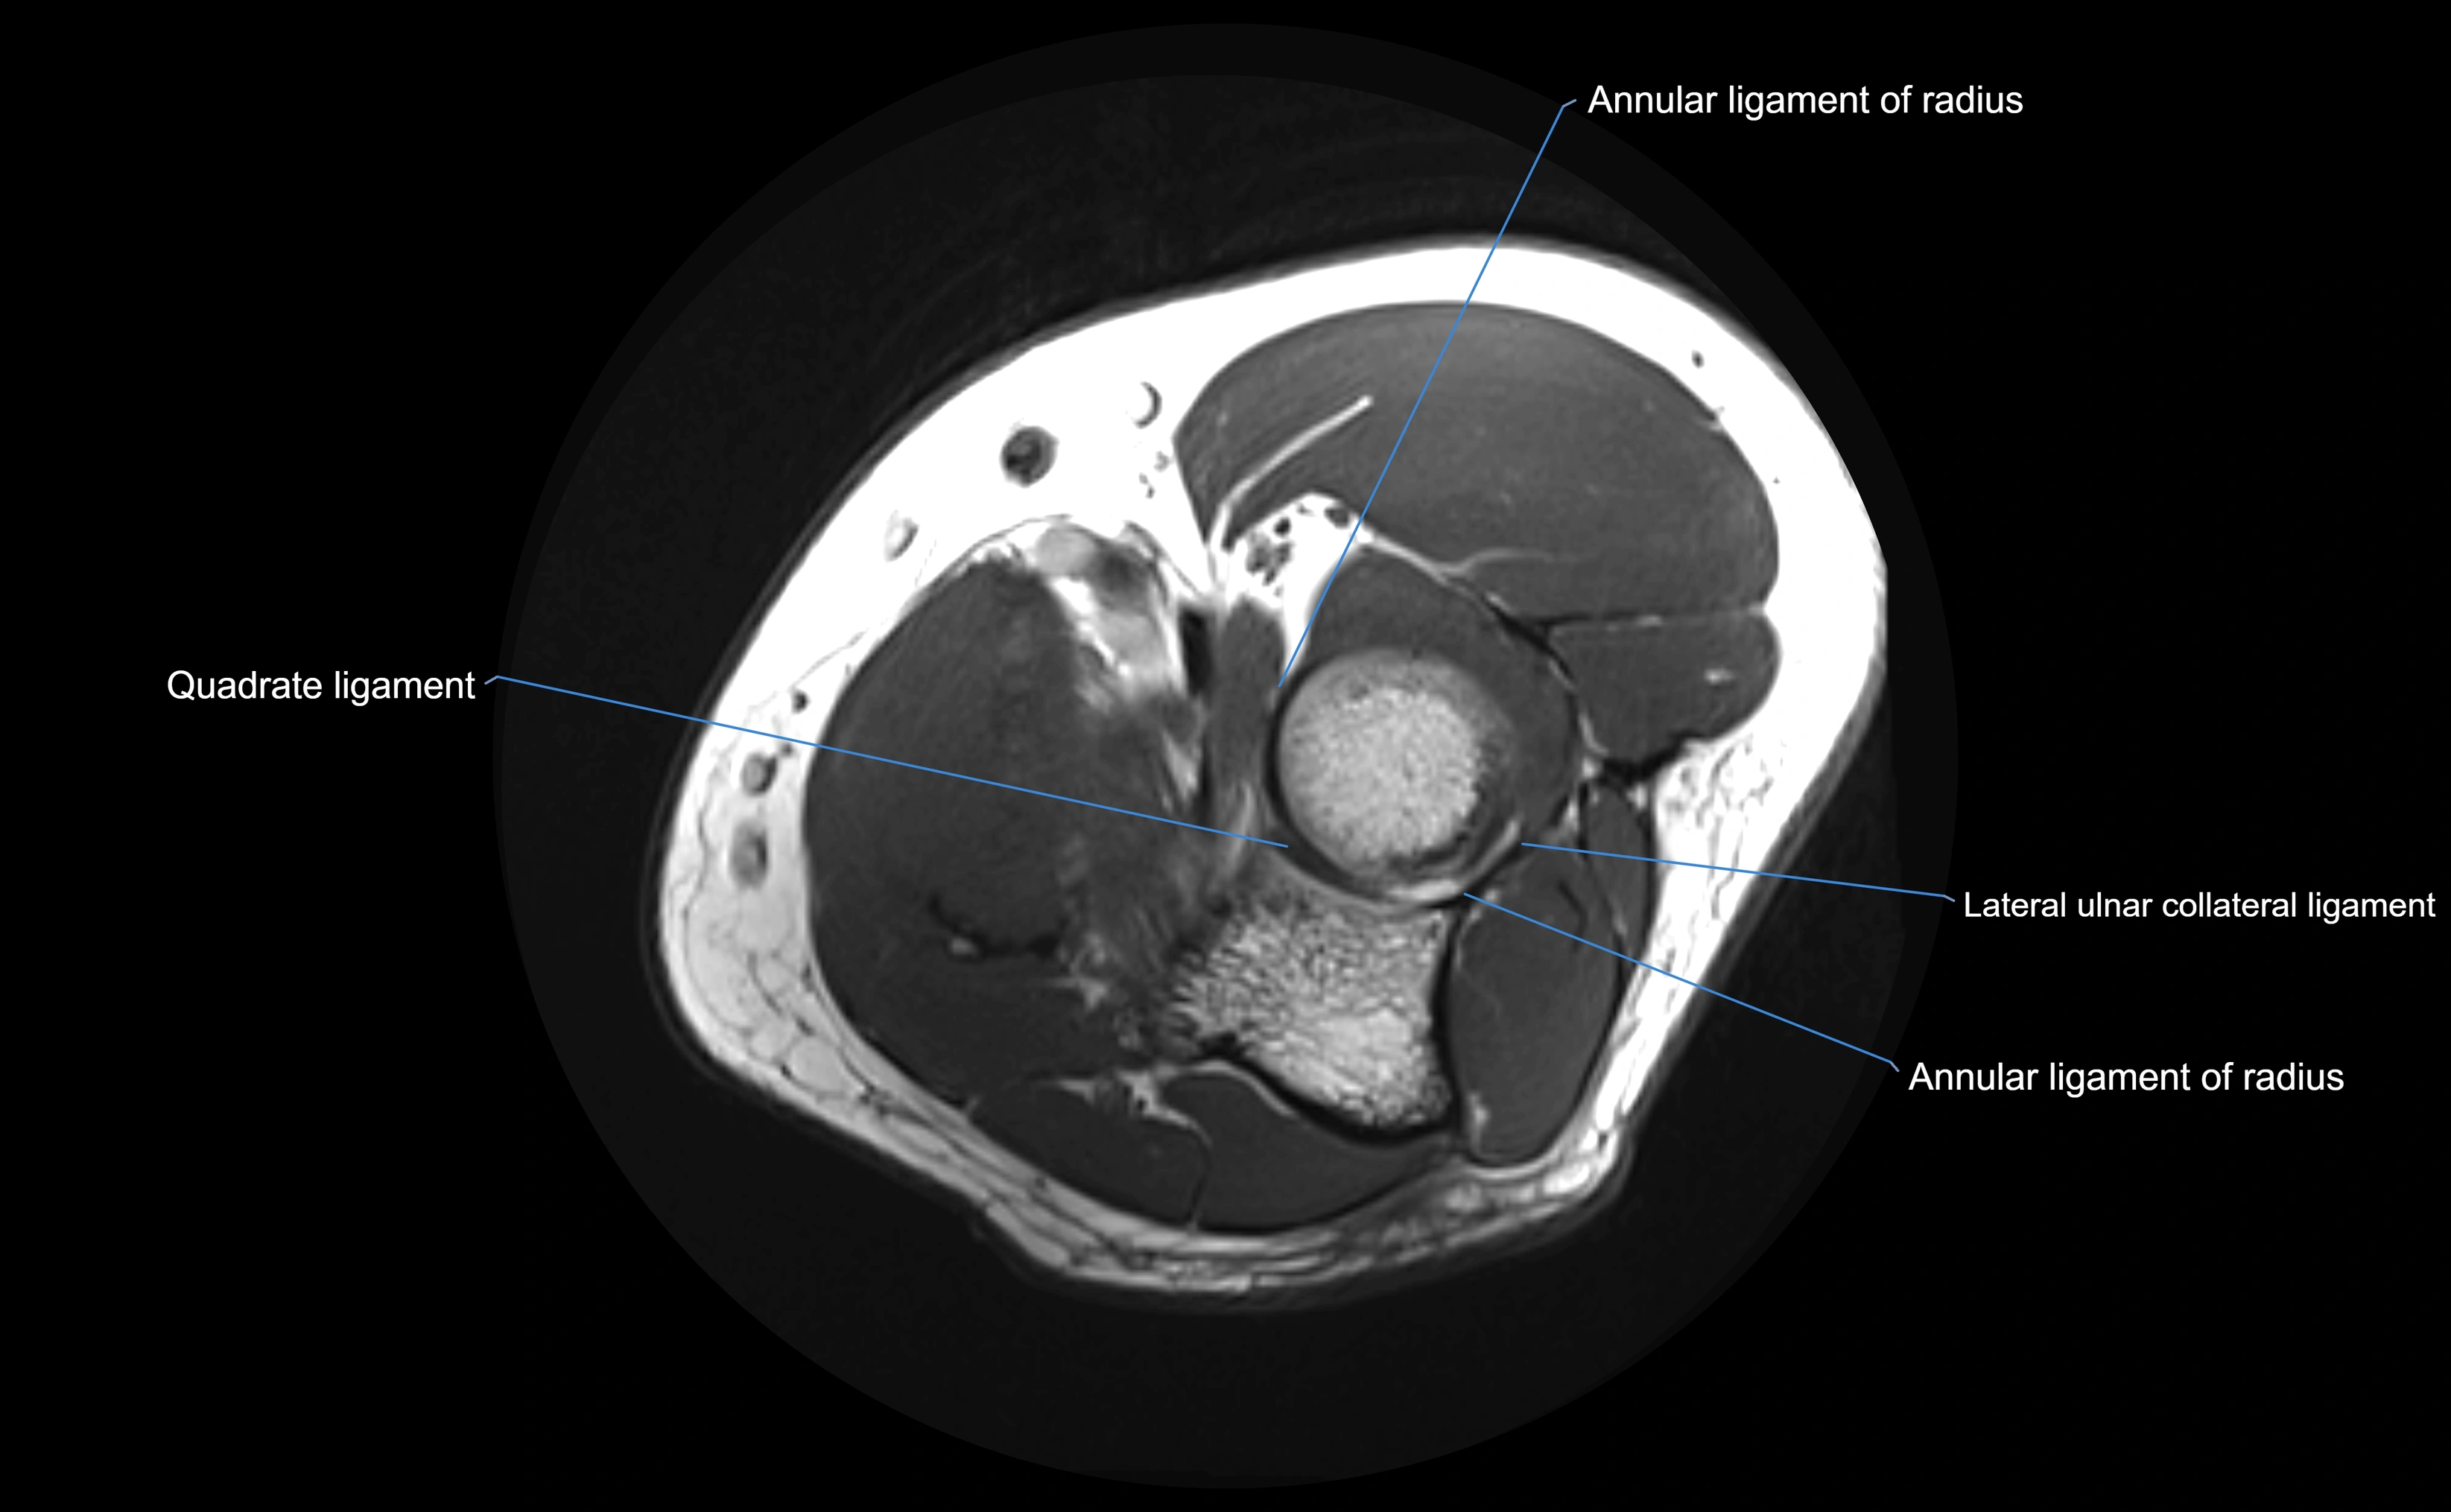

MRI images

image

MRI Appearance

T1-weighted images:

• Ligament: low signal intensity (dark), appearing as a continuous band around the radial head.

• Adjacent fat and marrow: bright, creating contrast with the ligament.

• Ligament: low signal (dark) with clear delineation from joint fluid.

• Fluid or edema: bright hyperintense, separating or surrounding the ligament in partial tears.